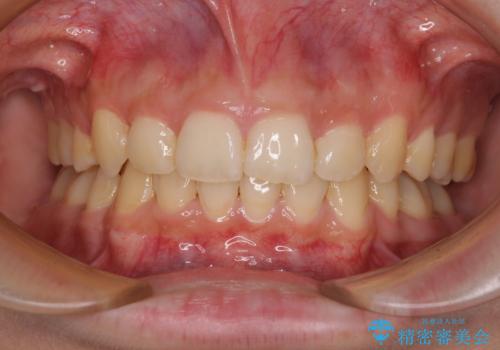

- 咬み合わせが悪いとのことで来院された患者様です。

ぱっと見はインビザラインによる矯正治療も可能と思われましたが、歯根が最も長い犬歯がクロスバイトになっており、インビザラインでは対応困難と判断され、ワイヤー装置にて矯正治療を行うこととしました。

クロスバイトになっている犬歯は、歯の移動に伴い装置を張り替えていくことで対応することとしました。